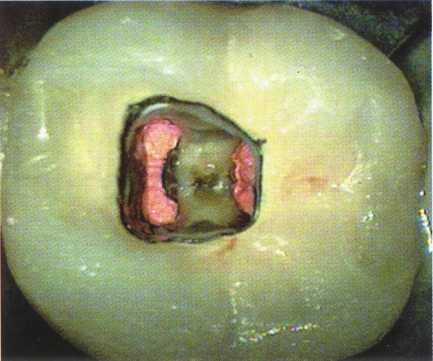

Unroo fing the Chamber

Unroofing the chamber and removing the coronal pulp facilitates the clinician's ability to visualize the chamber floor and aids in locating the canals. Complete removal of tissue and debris prevents discoloration and subsequent infection.

Unroofing the chamber and removing the coronal pulp (in vital cases) allow the clinician to see the pulpal floor. In cases of patent canals, most or all of the canal orifices may be easily located before the chamber is completely unroofed, but the clinician may nevertheless miss canals. In cases of calcification, performing these procedures increases the clinician's ability to visualize the pulpal floor and read the road map to the canal orifices detailed in the subtle color changes and patterns of calcification left by the receding pulp. This is extremely difficult or impossible to do through a "mouse hole" en-dodontic access.

Locating Canals

With complete eradication of the radicular contents, obturation of the radicular space, and good coronal seal to prevent ingress of bacteria, endodontic treatment should approach 100% success. However, this does not occur in reality. The second most common error in access, one that is often not noticed until a recall film is taken or the patient complains of persistent symptoms, is missed canals. The greatest teacher of endodontic anatomy is the microscope. Clinicians have learned that all roots (not teeth) with the exception of #6 through #11 may have two or more canals .z The MB2 canal of the maxil-

lary first molar is commonly referred to as an "extra" canal, but this is not the case-the fifth and sixth canals are the "extras." Without obtaining adequate access in shape, size, and location, locating the exceedingly complex anatomy present in posterior teeth becomes an exercise in futility.

Many of these canals are hidden under dentin shelves, pulp stones, protrusions, and restorative materials. Successful treatment requires adequate access, knowledge of the radicular anatomy, determination, and the assumption of two canals per root until proven otherwise.